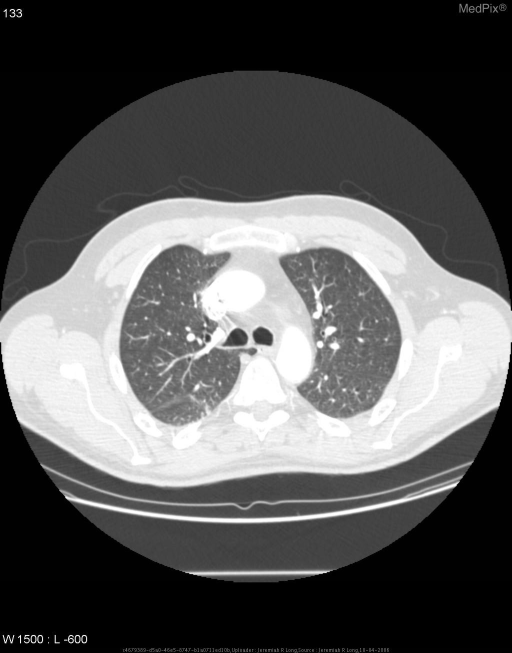

On CT Chest

CT is diagnostic and shows:

• The azygous fissure as a distinct 4-layered pleural line in the right lung apex

• The azygous vein at the inferior end of the fissure in a higher position than its normal tracheobronchial groove location

• Normal lung parenchyma within the lobe (no consolidation, no mass)

• CT confirms the benign nature and differentiates it from pathology

CT images below (MedPix) — axial sections showing azygous fissure and ectopic azygous vein:

CT chest axial — azygous fissure and lobe at right lung apex

Axial CT chest (lung window): The curvilinear azygous fissure is seen in the right lung apex, with the teardrop azygous vein at its inferior margin — classic azygous lobe anatomy.